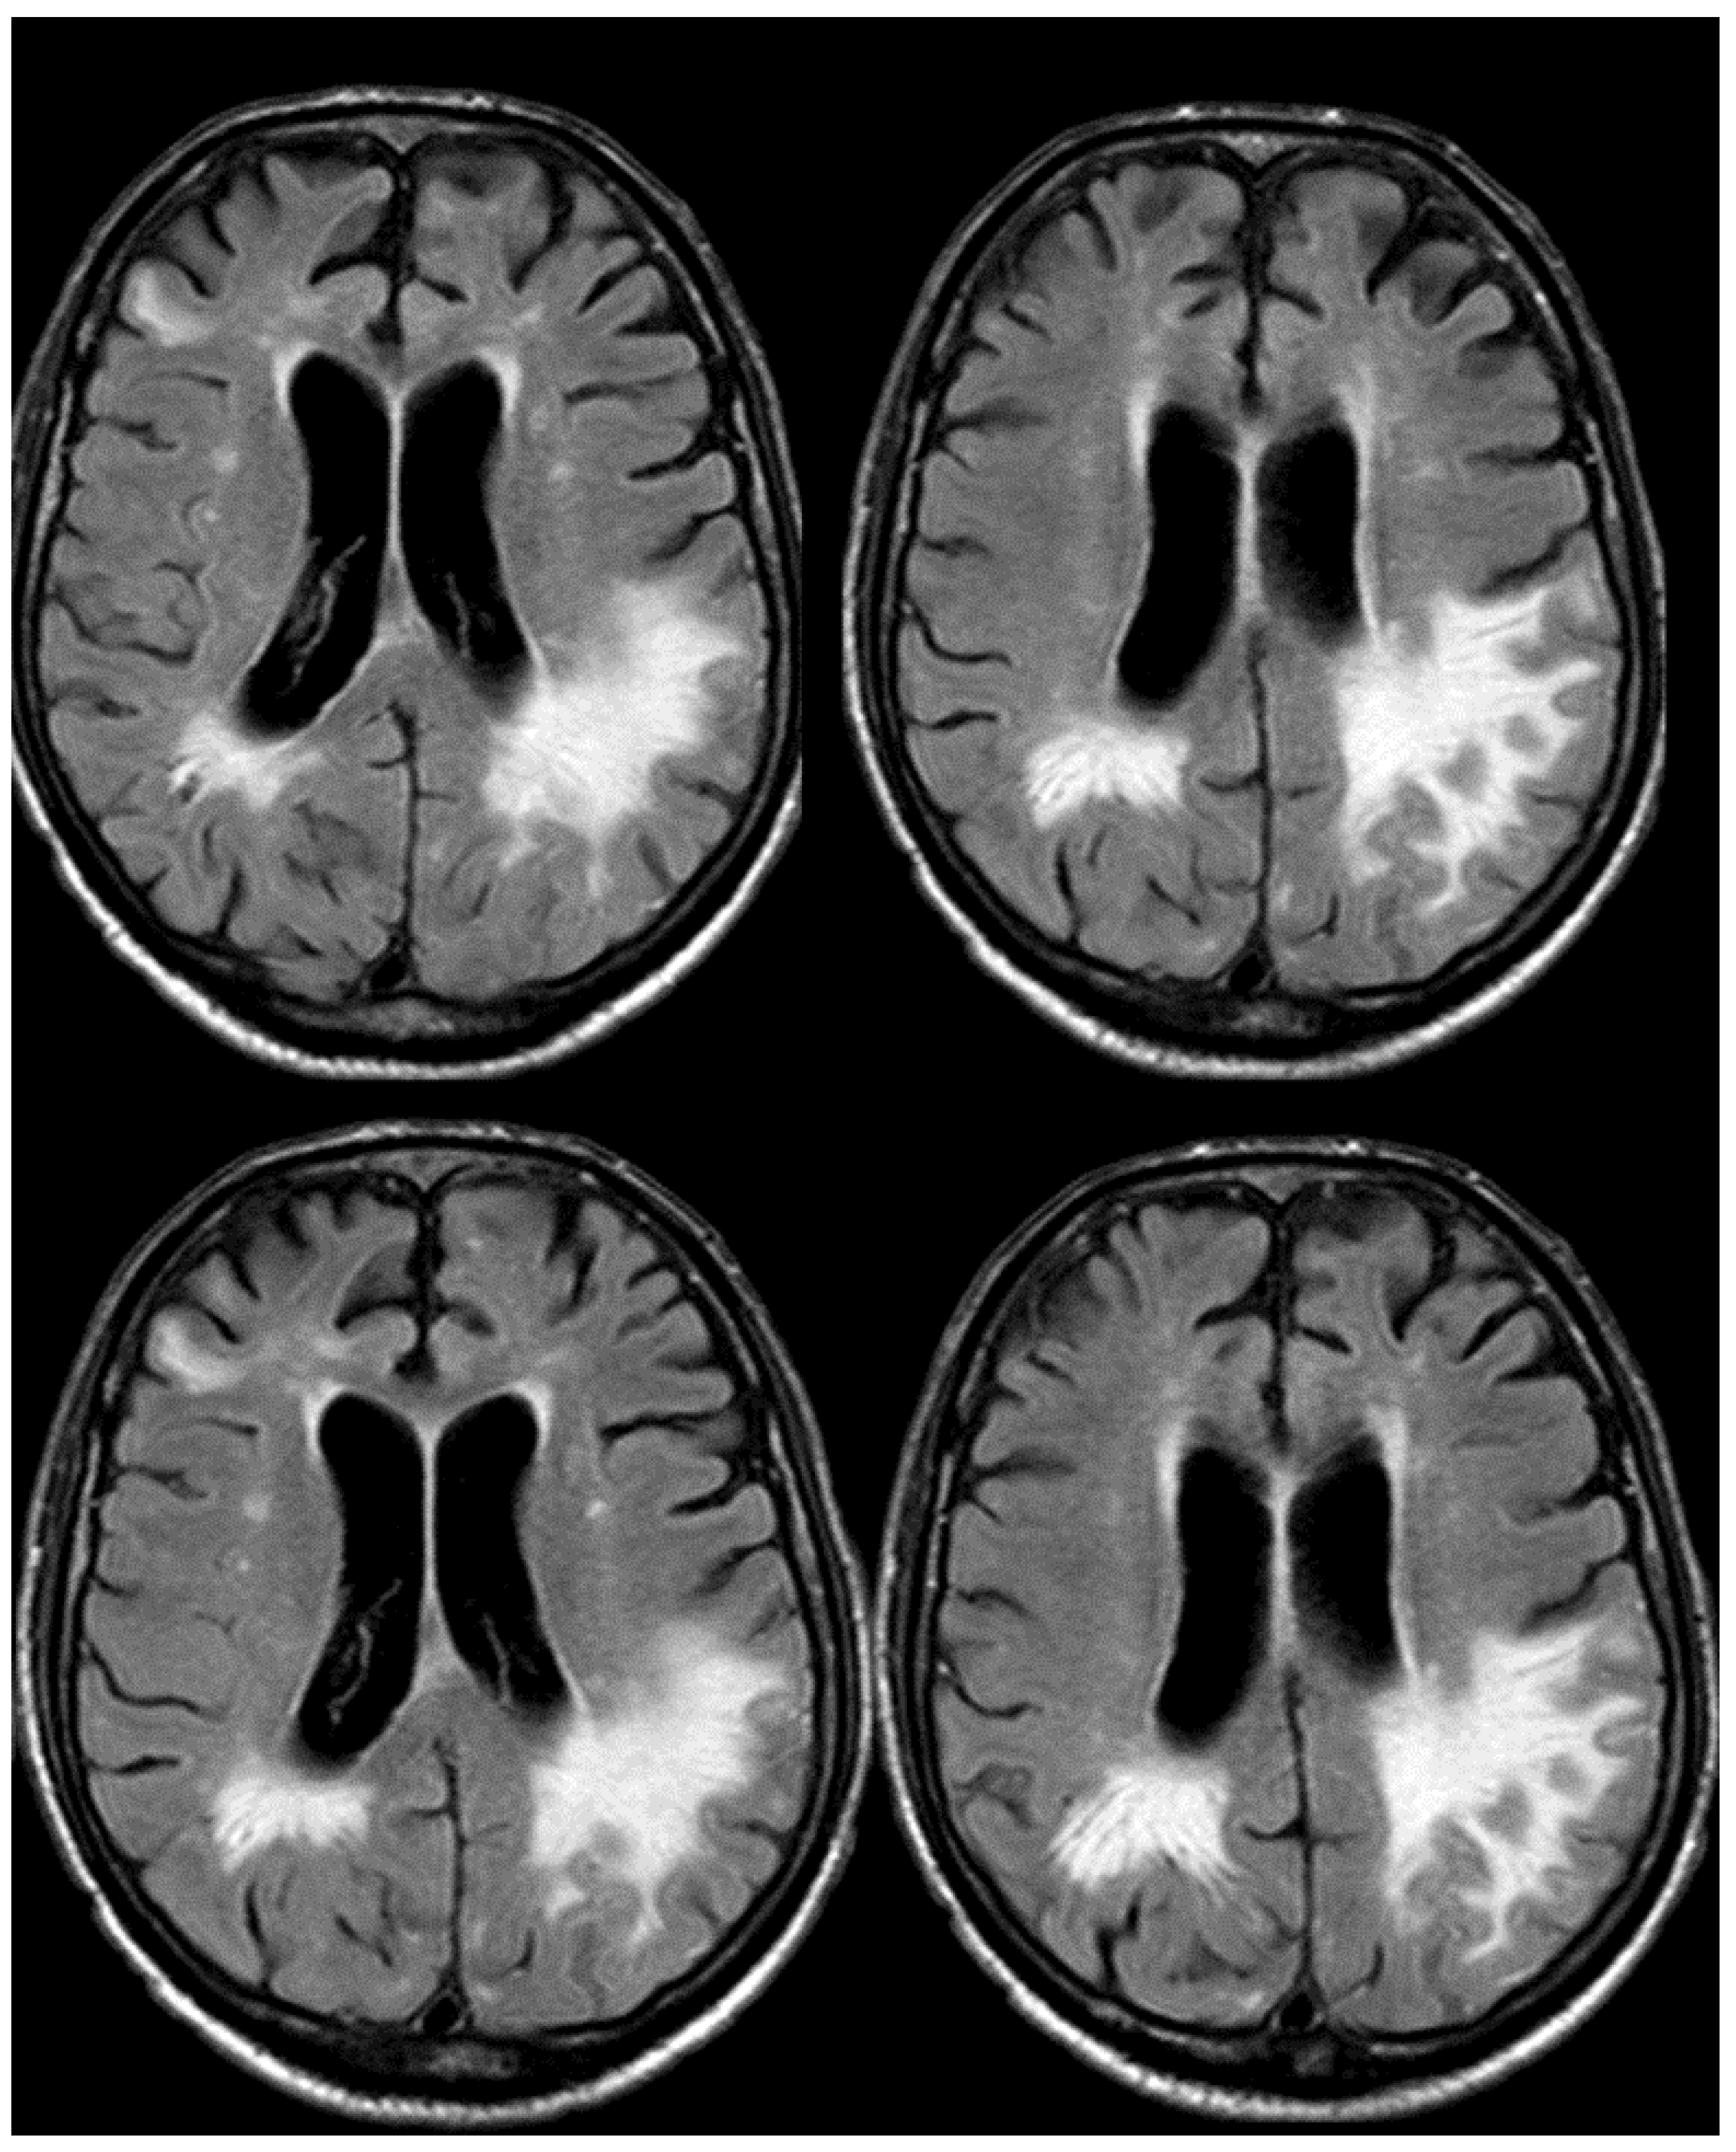

3. May 2014: CAA-Related Inflammation